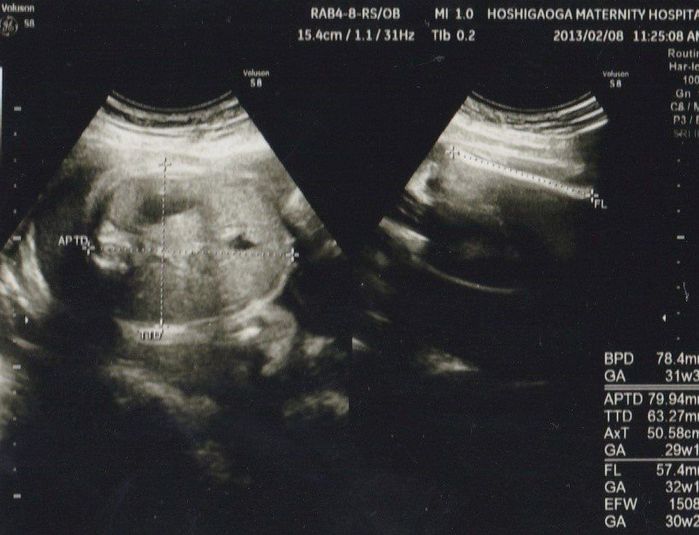

妊娠29週目のエコー写真

すっかり大きくなり、エコー写真には全身が入らなくなっていました。推定体重は1508g。左側は腹部で右側は大腿骨の写真です。この週の健診で、性別がまさかの女の子に確定しました。前回、「男の子かもしれない」というのは何だったのだろう! とびっくりしましたが、長女は赤ちゃんが女の子だと聞いて喜んでいました。